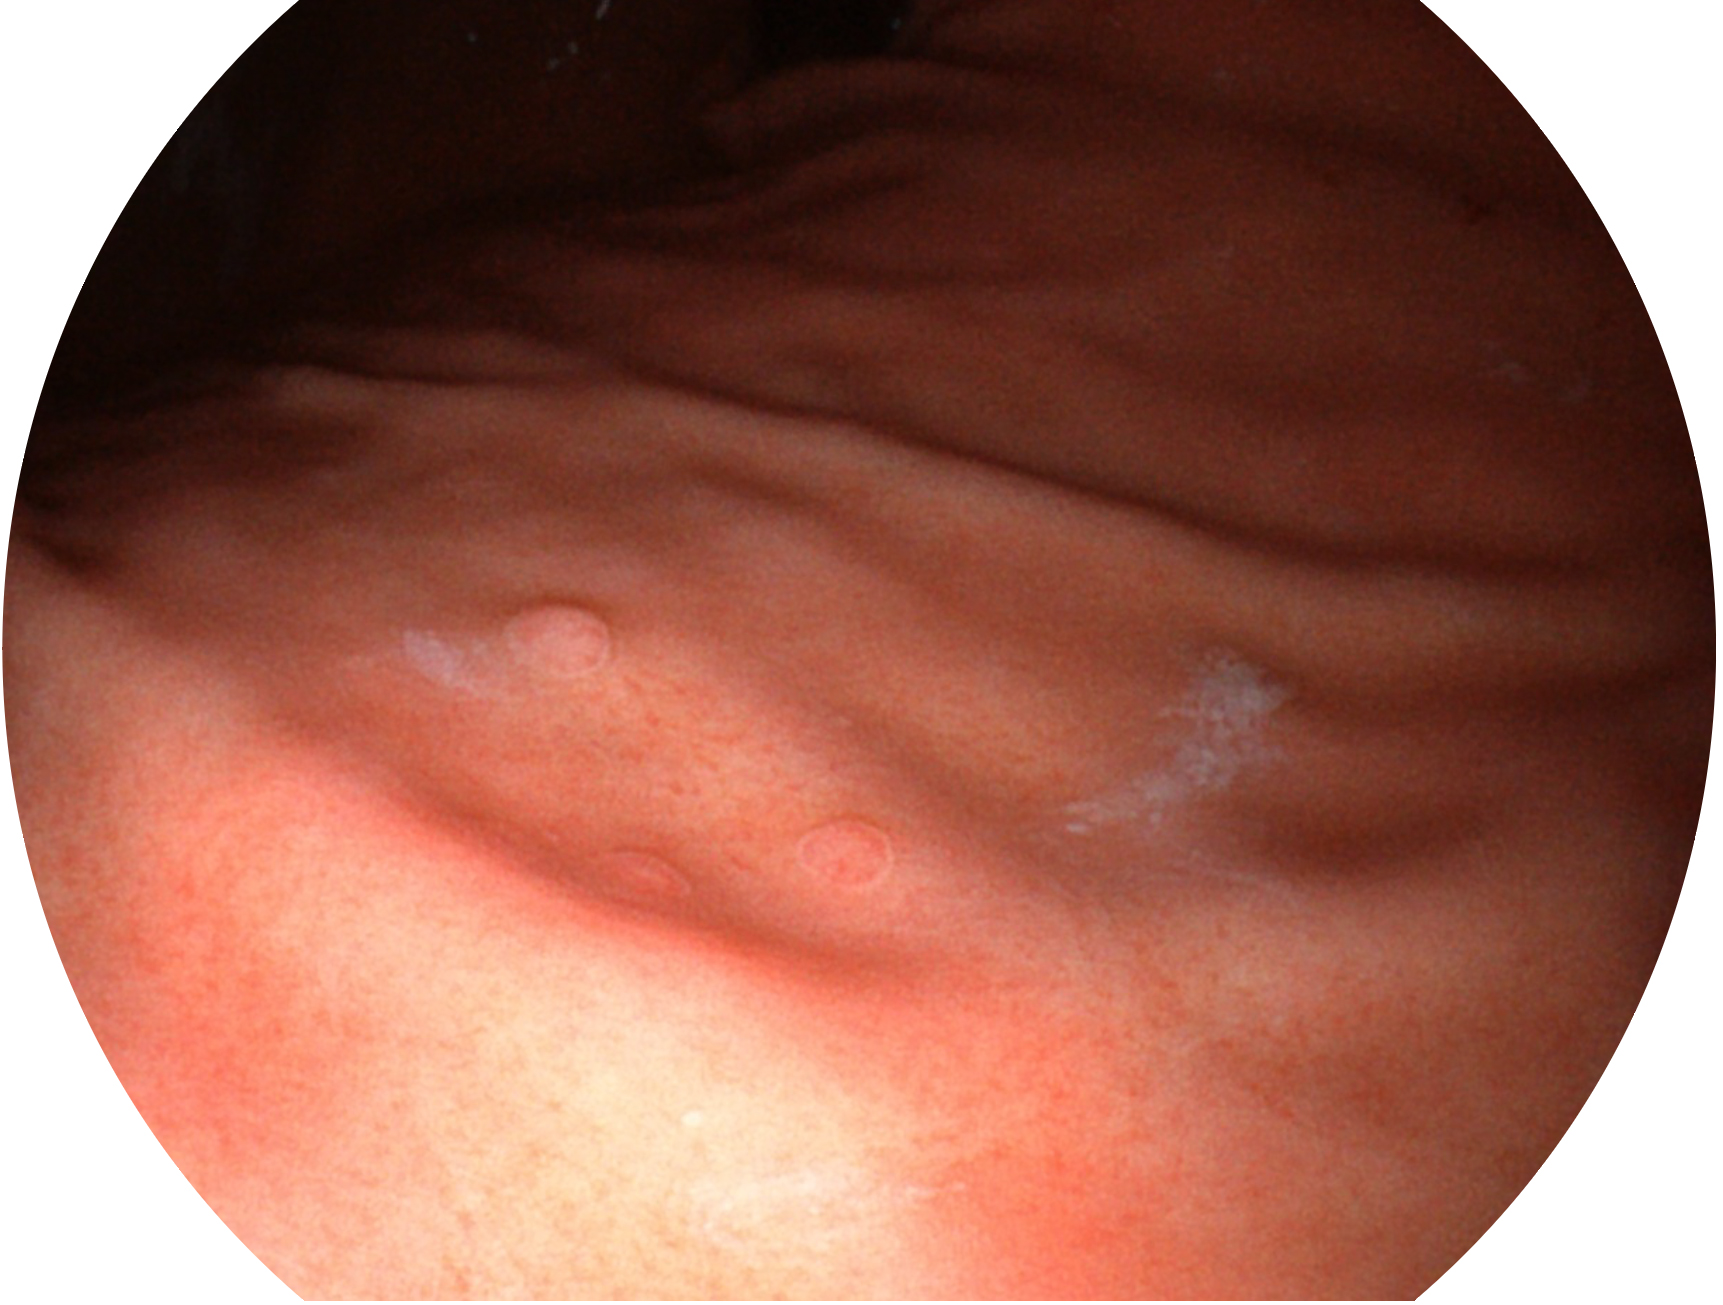

乐玩lewin国际新开发的内镜染色技术,主要是基于多波长LED 光源的开发,VLS-55Q 四波长LED 光源是由四个不同颜色的LED光按照相应照明模式所规定的特定发光比例进行合束后形成,合束后形成的照明光的光谱由红光、绿光、蓝光及蓝紫光这四个不同的波段范围构成。具有更高光谱自由度,通过光谱比例的控制,实现了聚谱成像技术,英文全称为“Spectral Focused Imaging, SFI”,缩写为“SFI”和光电复合染色成像技术,英文全称为“Versatile Intelligent Staining Technology, VIST”,缩写为“VIST”。